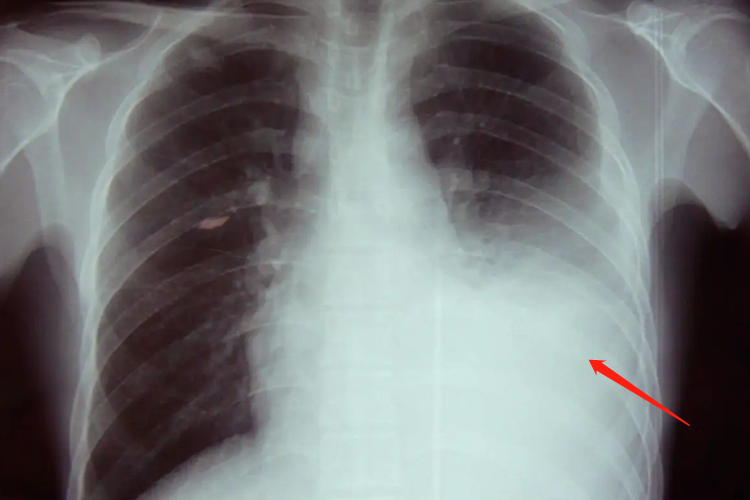

正常胸透图片是由黑、白两种颜色组成,通过黑、白颜色分布来进行观察。如分布在两边好大一片黑色,犹如一扇窗户的位置为肺,由于它能让X线透过,所以在胸片上呈现出黑色。在两肺之间夹杂着一大片白色,此处为心脏,医学上把这一带叫作纵隔,其中有心脏、大血管、气管等。由于它们密度大,致使X线无法透过,或是透过的X线较少,因此在胸片上呈现出白色。

但多是黑、白跌倒则预示疾病,如该黑的地方变白了,或是该白的地方变黑了,这就是异常。前者常见的有炎症、结核、肿瘤、胸腔积液等,后者有肺气肿、气胸等。